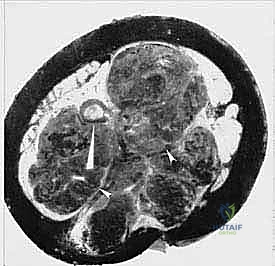

الخطوة الثالثة: الشق الخلفي ورفع السديلة

يتم الآن قلب المريض قليلاً لإجراء الشق الخلفي. يتم رفع الجلد والدهون وعضلة الألوية الكبرى (Gluteus Maximus) ككتلة واحدة (السديلة الخلفية)، مع الحفاظ على التروية الدموية الخاصة بها لضمان عدم تموتها لاحقاً.

الخطوة الرابعة: قص العظام (Osteotomy) وفصل الحوض

باستخدام مناشير عظمية متقدمة، يتم فصل عظام الحوض عن العمود الفقري (عند المفصل العجزي الحرقفي) وفصلها من الأمام (عند الارتفاق العاني). يتطلب هذا دقة متناهية لضمان استئصال الورم بالكامل دون المساس بالأعضاء الداخلية في الحوض (مثل المثانة والمستقيم).